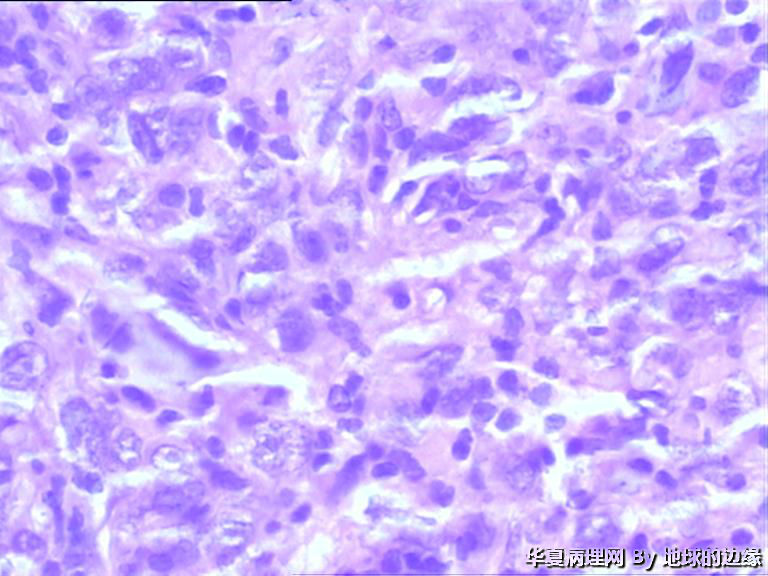

右肱骨肿瘤待查

病人女性,48岁

MRI示:右肱骨肿瘤待排,包块大小为10x8cm,活动度差,边界欠清,鱼肉组织(白色),肿块侵犯至骨外    组  织。

恶性。是转移还是原发,是骨肉瘤还是浆母?需要进一步资料并标记。

考虑肉瘤,转移癌也排除一下吧

目前Vimentin阳性,P53阳性,AFP,EMA,CK7,CK20,E-ca,CR,PLAP,CD99,ER,PR,CEA,均阴性,只是没做淋巴瘤这一套了